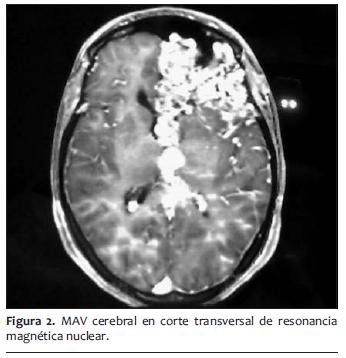

Presentaba antecedentes quirúrgicos anestésicos de cesárea de coordinación hace 3 años, con anestesia peridural sin incidentes y antecedentes personales de epilepsia sintomática secundaria a MAV cerebral gigante frontal izquierda diagnosticada 12 años atrás, sin indicación quirúrgica por alto riesgo, en tratamiento con clonazepan 4 mg/día y valproato, que suspendió en el embarazo. La resonancia nuclear magnética informaba voluminoso nido de MAV a nivel frontal izquierdo con gliosis locoregional asociada (figuras 1 y 2). Voluminosos troncos de drenaje superficial y profundo con dilataciones venosas. Angioma cavernoso a nivel frontal subcortical del lado derecho paraventricular.